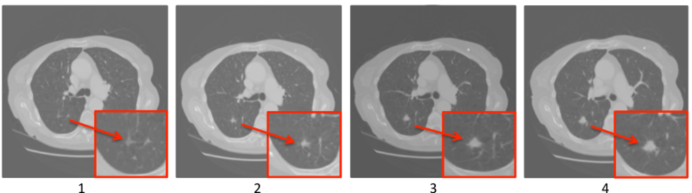

In this work we set out to mimic the reading process carried out by radiologists, who would typically explore all the slices in the stack and draw inferences about the likely presence of a nodule by picking up changes in radiological appearance between adjacent slices. The need for integrating inter-slice information for nodule detection and characterisation has often been emphasised in the literature (Golosio et al., 2009; Tan et al., 2011; Messay et al., 2010). As an illustrative example of this, Figure 1 shows four adjacent cross-sectional slices extracted from a thoracic CT scan. All images contain a pulmonary nodule whose morphological characteristics differentiate it from the surrounding normal tissue. Our hypothesis is that learning imaging features that capture such inter-slice spatial correlations can eventually introduce performance gains in nodule detection. In order to address this problem, we propose an artificial neural network that combines the representational power of CNNs with the capability to learn dependencies in sequential data that is typical of recurrent neural networks (RNNs) (Hochreiter and Schmidhuber, 1997). RNNs have achieved tremendous success in solving challenging sequential problems like machine translation and speech recognition (Bahdanau et al., 2014; Graves and Jaitly, 2014; Sutskever et al., 2014). More recently, multi-dimensional RNNs have shown state-of-the-art performance in scene lebeling in 2D images (Byeon et al., 2014), volumetric image segmentation (Stollenga et al., 2015; Poudel et al., 2016) and modeling the distribution of natural images (van den Oord et al., 2016).

Refer to caption

Figure 1: Internal anatomical structure of a pulmonary nodule as shown in four transverse consecutive sections of a CT scan. The morphological characteristics of the nodule change gradually across slices.